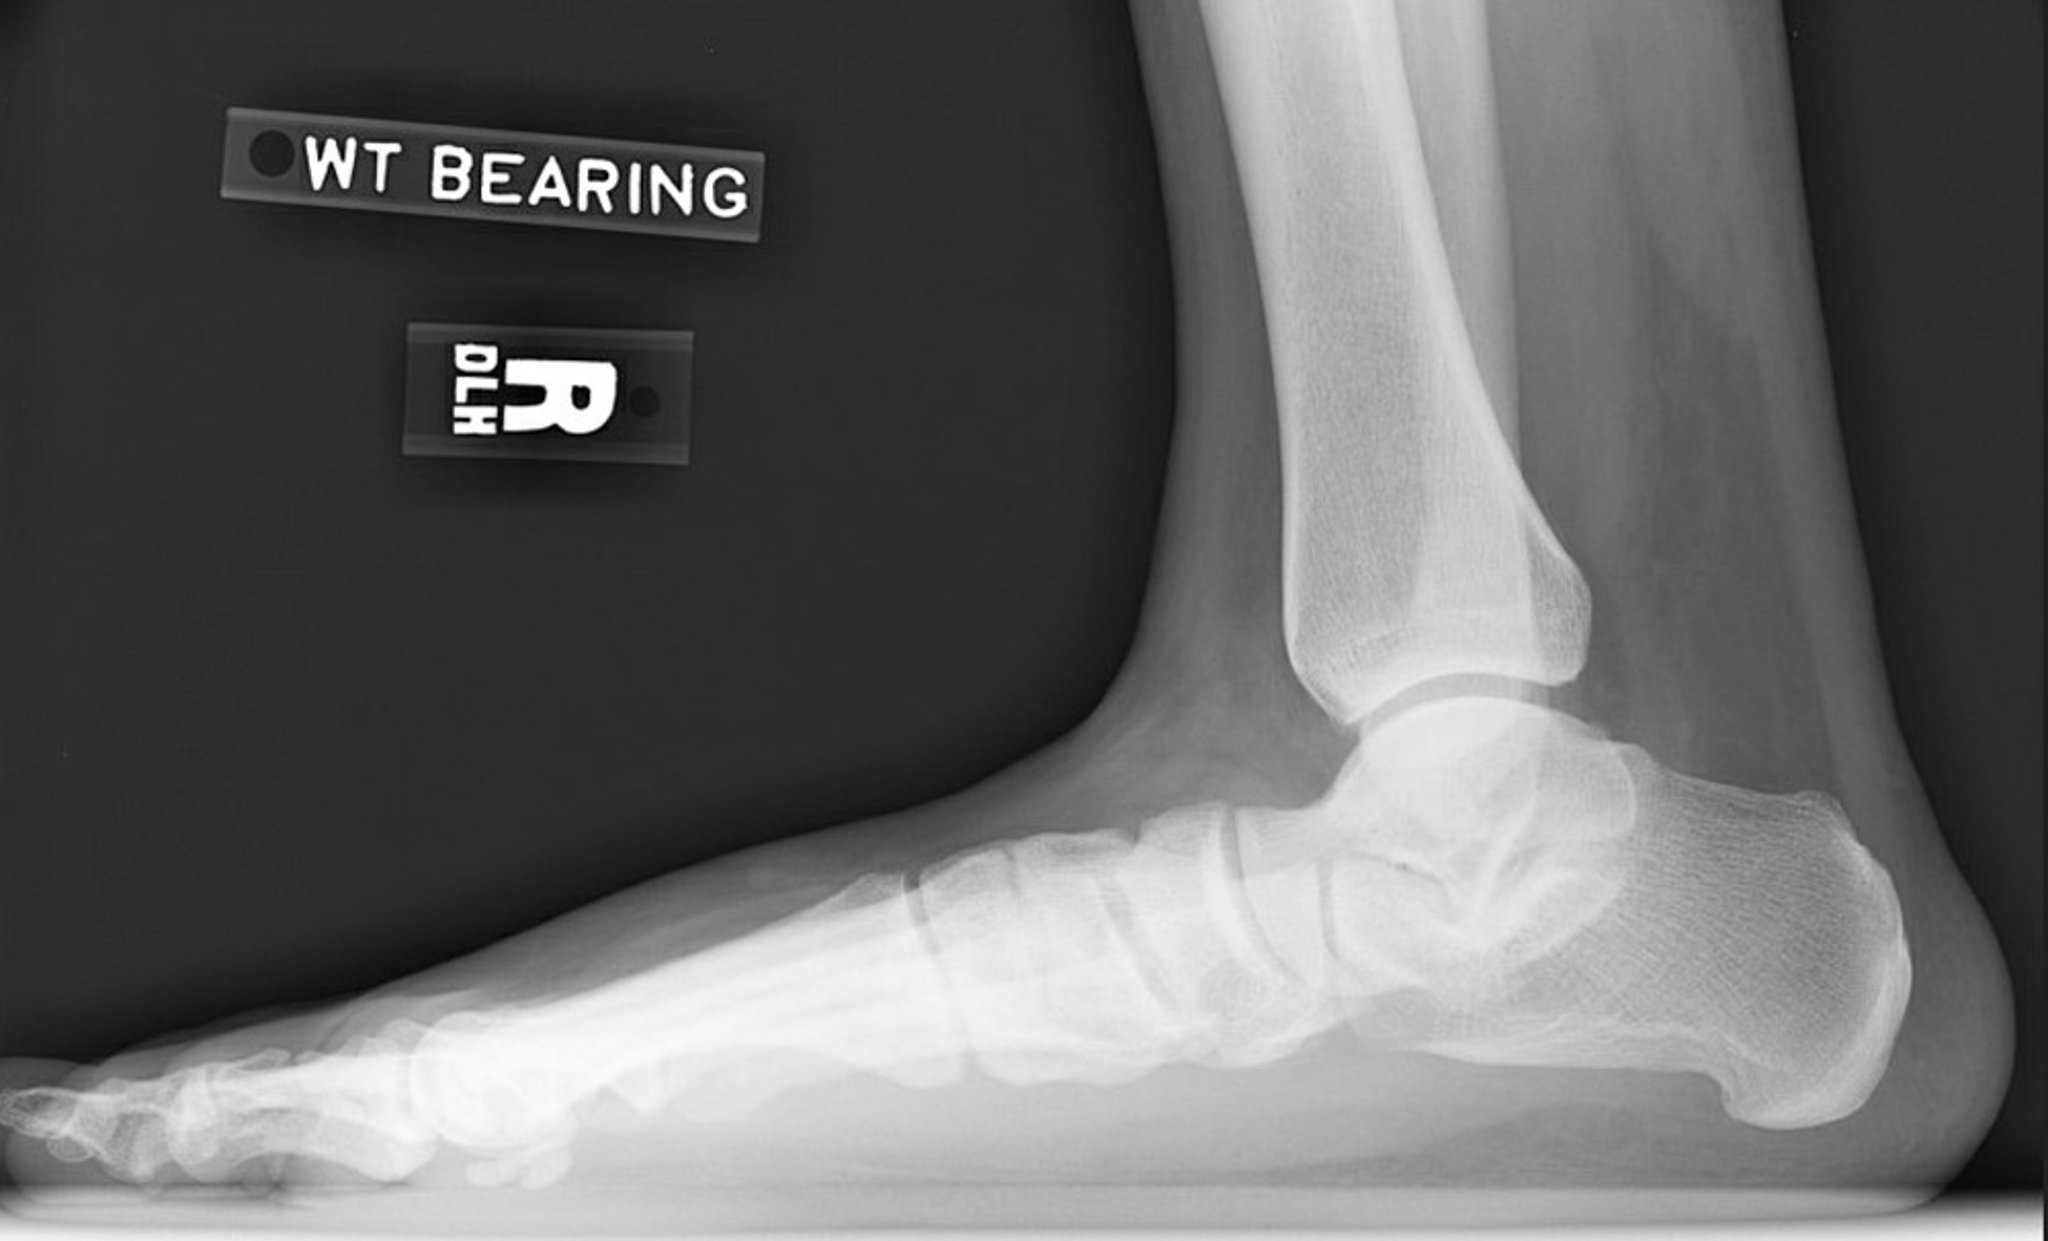

Radiographie du pied plat

Radiographie latérale du pied droit montrant une perte de hauteur de la voûte plantaire. Notez la diminution de l'angle d'inclinaison du calcanéum et la diminution de l'angle de déclinaison talaire. L'articulation sous-talaire est réduite mais l'articulation de la cheville est relativement préservée.

Image courtoisie de James C. Connors, DPM.